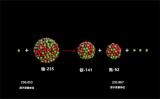

由不可切除转化为可切除 中国第二例钇[90Y]树脂微球治疗患者成功切除肝脏肿瘤

介入治疗成为这类患者普遍的非治愈性疗法而被采用,而钇[90Y]树脂微球精准介入放射治疗是融合介入和精准内照射治疗的一个典范。介入内放射治疗(SIRT)是医师将钇[90Y]树脂微球注射液注入肝脏血管,释放高能量β放射线,近距离瞬时杀灭肿瘤细胞,对正常肝组织和周围环境几无影响。 2022-07-01 放射性同位素

抗肝癌创新药放射性同位素钇[90Y]微球注射液正式上市,为肝癌患者带来希望

滕皋军院士表示,介入治疗是中晚期肝癌治疗最常用的方法。对比常用经动脉化疗栓塞(TACE),SIRT利用类似的血管介入治疗方式,起到内放射治疗的效果。在SIRT治疗中,钇[90Y]放射性同位素搭载树脂微球,可以实现肿瘤全面、精准的覆盖,保证了SIRT治疗的疗效。 2022-06-20 放射性同位素